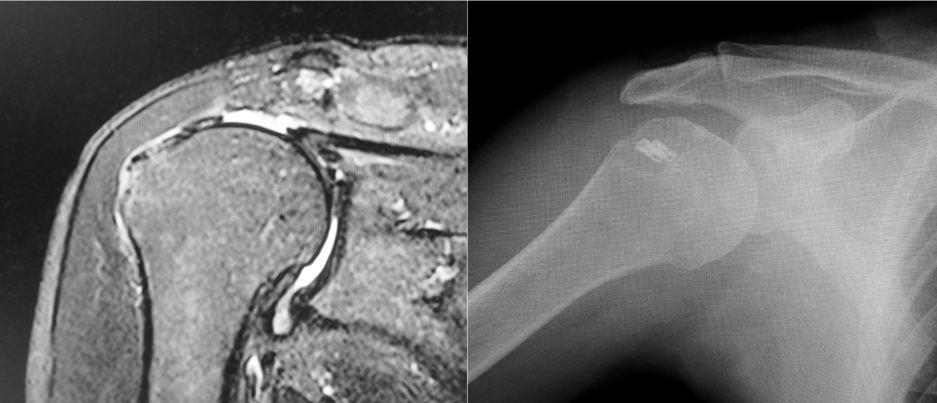

棘上筋が有している肩関節外転作用はそこまで大きいものではありません。 その理由は 上腕骨頭中心から停止部までの距離が短いため です。 そのため、肩関節外転運動では三角筋に依存している形になります。腱板損傷(腱板断裂)けんばんそんしょう・けんばんだんれつ というのは 肩のインナーマッスルである腱板筋群(後述しますが4種類あります)のスジが切れてしまうという状態 です。 スジが切れてしまうなんて、よっぽどのことだと思われるかもしれません。 しかし、実際は四十肩・五十肩と思いきや、腱板断裂だった・・・という人が非常に多いんです多くの場合、 棘上筋の腱から断裂 します。 そして徐々に断裂は後方、場合によっては前方、へと拡大していきます( 図A )。 転倒して肩を強打するなど大きな外傷で起こります。 中年以降になると重いものを持った時など軽微な外傷でも起こります。 加齢や長年にわたる肩の酷使で、徐々に擦り切れます。 などがあります。 腱はレントゲンには写らないので

腱板損傷 読影のポイント 整形外科 スポーツ整形の画像診断 読影を学び 要点をついた撮影法を考える

鏡視下腱板修復術 肩腱板断裂に対する手術 Ar Ex 尾山台整形外科